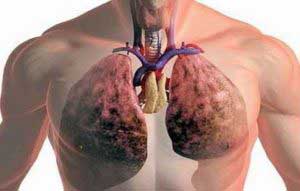

Туберкулоза - широко разпространено заболяване, което засяга все повече хора всяка година. увеличение на честотата може да се дължи на неговата адаптивност към различни лекарства, така че ефективно лечение изисква използването на различни методи, включително и народни средства. Това ще се отървете от новите форми на заболяването.

Основният източник на болестта - е болен човек, е бил изолиран от неговите микобактерии дихателните пътища. За инфекция на практика няма бариера, тъй като е в състояние да бъдат прехвърлени чрез праха, въздухът и въздуха капчици. Най-често страдат от това заболяване по-възрастните хора на възраст над 60 години и малки деца до 3 години. Трябва да се отбележи, че TB също се счита за доста често срещано заболяване сред хората без дом и затворници.

Когато заболяването става сериозен етап и засяга тялото на пациента за втори път, след това може да бъде метаболитно разстройство, остра кашлица с кръв и слюнка, болка в гърдите и така нататък. Ако човек е заразен с туберкулозата микобактерии, това не означава непременно, че се появява патологията на белия дроб. Това може да се случи само ако слаба имунна система.

Белодробна туберкулоза може да се осъществи със следните усложнения: